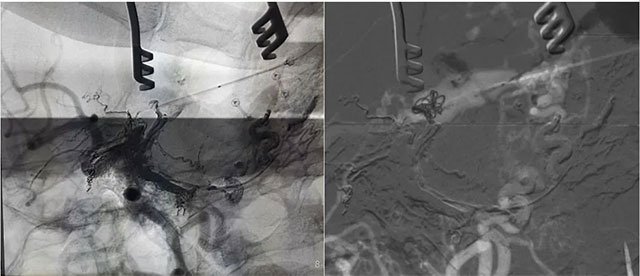

▲ 造影确认位置后,穿刺左侧横窦,置入 Echelon10 微导管

▲ 再次造影确认位置后,填入 HELIX 6/20弹簧圈

经左侧股动脉以单弯造影管超选至左侧颈总动脉造影明确静脉穿刺点入路,予以穿刺针穿刺成功后造影明确在位,随后 Echelon 10微导管到位横窦,填入一枚弹簧圈做塞子,造影明确位置后,缓慢注入 Onxy18胶 5毫升,铸胶弥散良好,通过静脉逆向弥散至部分供血动脉内。复查造影,见瘘口完全被栓塞,引流静脉消失,手术成功。